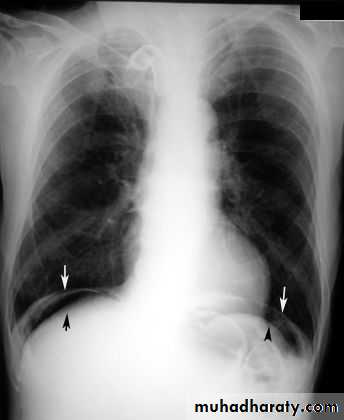

Pneumoperitoneum

Defined as free gas in the peritoneal cavityThe commonest cause is perforated peptic ulcer and two-thirds of such cases are recognizable radiologically

Pneumoperitoneum under the right hemidiaphragm is usually easy to recognize, but free gas under the left hemidiaphragm is difficult to recognize because of the overlapping gas shadows of the stomach and splenic flexure.

Gas under the diaphragm is much easier to diagnose on an erect chest film than on an upright abdominal film

Gas in an abscess

It may form either small bubbles or larger collections of air , both of which could be confused with gas within the bowel.Fluid levels in abscesses may be seen on a horizontal x-ray film.

Subphrenic abscess cause elevation of the diaphragm, pleural effusion and pulmonary collapse/consolidation